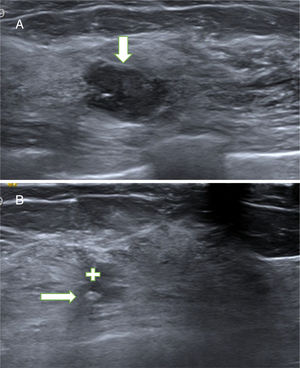

A. Papiloma atípico (PA). Paciente de 54 años con nódulo no palpable en la mama izquierda que se detectó en mamografía y ecografías de cribado. La ecografía mostró un nódulo sólido (hipoecogénico) de contornos polilobulados, parcialmente bien circunscrito, hallazgo BIRADS 4A. El diagnóstico de sospecha fue de fibroadenoma. La BAG obtuvo el diagnóstico de PA. La extirpación con BAV confirmó el diagnóstico de PA. B. Cicatriz con marcador. Control ecográfico a los 35 meses. La ecografía mostró un área irregular hipoecogénica (cruz blanca), estable desde el primer control a los 2 meses, relacionada con la fibrosis secundaria a la BAV. En el interior de la cicatriz se objetiva el marcador metálico (flecha) que se colocó después de la BAV para facilitar la localización del lecho de la biopsia por si el resultado hubiese sido un carcinoma papilar.

Solamente en un PA diagnosticado con BAG se colocó marcador en el lecho de la biopsia inmediatamente después de la BAV (fig. 2B).

La infraestimación a CP del PA diagnosticado con BAG oscila alrededor del 40%, por eso suelen extirparse con cirugía24. La probabilidad de infraestimación del PA es menor cuando el patólogo no duda de la benignidad en los cilindros obtenidos con la BAG y existe una adecuada correlación radiopatológica (lesiones pequeñas, BIRADS 3 o 4)8,24. En nuestra serie, el patólogo consideró adecuado que se realizara la extirpación con BAV de los 3 PA. La BAV confirmó la benignidad en los 3 PA y no hubo recaídas en el seguimiento (fig. 3 A y B). Pensamos que este manejo es razonable aunque no haya sido descrito previamente en la literatura.

Nuestra actitud también fue la misma en los PB o pPB extirpados con BAV cuyo resultado fue de PA. Esto ocurrió en 6 PA (6 pacientes): 2 PB diagnosticados con BAG (BIRADS 4A), 3 pPB (BIRADS 3) y un PD (BIRADS 3). Se decidió realizar seguimiento ya que el diagnóstico de la BAV no mostró sospecha de malignidad (fig. 4 A y B). Este manejo lo hemos visto recogido en la literatura solo parcialmente en el trabajo de Kim et al.17. De 65 lesiones papilares diagnosticadas con BAV, se obtuvieron 7 PA, de los cuales se extirparon quirúrgicamente 5 con el resultado de 4 PB y uno sin lesión histológica, y solo en los otros 2 PA realizaron seguimiento sin encontrar infraestimación.